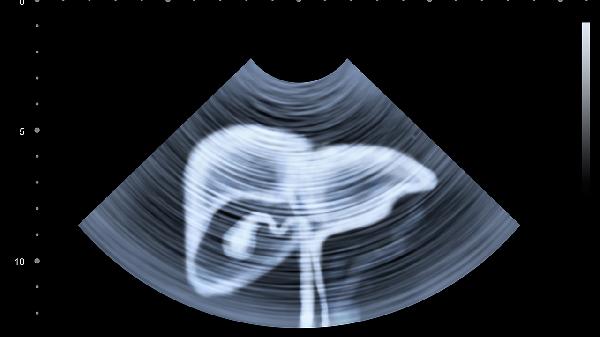

肝功能异常患者需定期复查肝功能、肝脏超声等检查,监测病情变化。保持良好心态,避免焦虑抑郁情绪影响康复。出现明显乏力、黄疸加重、腹水等症状时应及时就医。在医生指导下可适当使用护肝药物如复方甘草酸苷片、水飞蓟素胶囊、双环醇片等,但不可自行滥用药物。注意个人卫生,接种乙肝疫苗预防病毒感染。